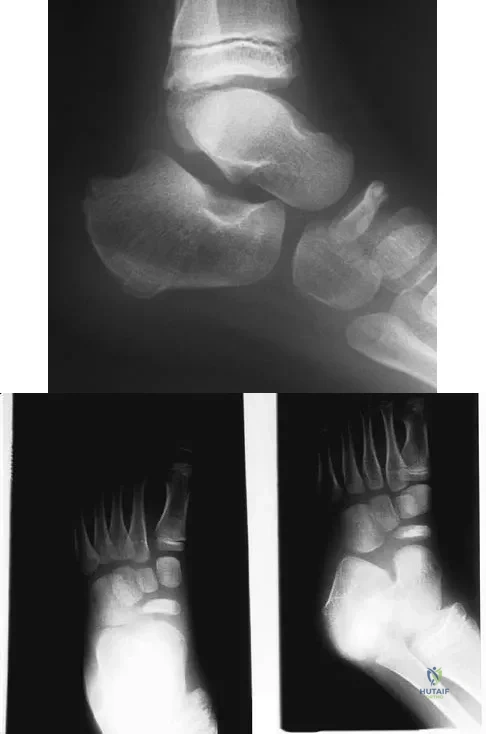

Figure 11 shows the radiograph of an otherwise healthy 22-year-old man who sustained a midfoot injury in a motor vehicle accident 9 days ago. Treatment should consist of

A 75-year-old woman reports foot pain and states that her foot has become progressively "flatter" in the past 3 years. Custom inserts and physical therapy have failed to provide relief. Examination reveals a flexible hindfoot and mild heel cord contracture. The patient is able to perform a single limb heel rise. Weight-bearing radiographs are shown in Figures 21a through 21d. What is the most appropriate surgical management?